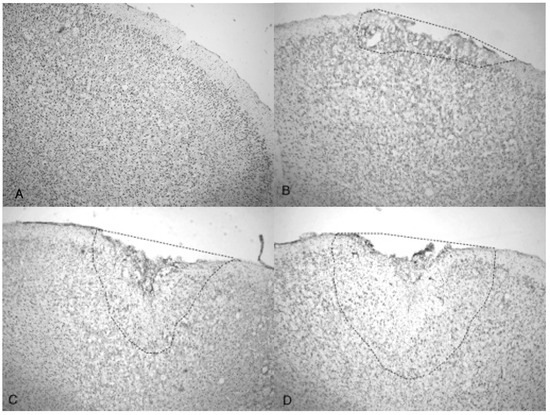

Microphotographs of cresyl violet stained tissue from 3.4 bar TBI treatment (Figure 4A,C) show indentation and fragmentation of the cortex exactly where the acoustic wave was administered to two separate rats. The opposing panels (Figure 4B,D) show intact, unaffected tissue in the contralateral cortex at the same stereologic orientation (approximately +3.0 anterior to bregma). In addition, the cells in Figure 4A,C appeared to be more sparsely distributed in the damaged region, suggesting neurodegeneration and disruption of neural pathways. Similar histological profiles were observed with 4.2 bar sections.

Figure 4. Microphotographs show the tissue from the frontal cortex visualized with cresyl violet from 60 day-old Han-Wistar rats, 10 days post-injury. Images indicate the damage from the acoustic wave 3.4 bar TBI targeted left frontal cortex as shown in the left panels (A,C) and compared with the contralateral, unaffected right frontal cortex (B,D) from the matching animals. Panels (A,C) show indentation and fragmentation of the cortex where TBI was administered while panels (B,D) show intact, unaffected tissue. In addition, the cells in A and C are more sparsely detected, suggesting neurodegeneration and disruption of neural pathways in these animals. All photomicrographs were taken at 40× magnification.